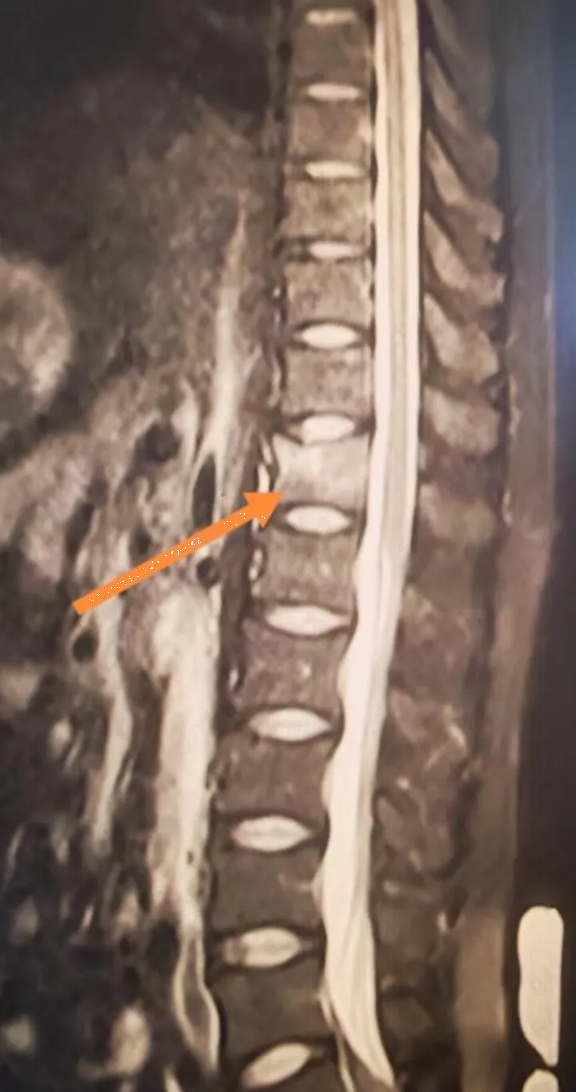

Kết quả chụp MRI khiến anh hoàn toàn sững sờ: gãy xẹp đốt sống T12.

Các xét nghiệm tiếp theo cho thấy kết quả còn gây sốc hơn chỉ số Z-score L1-L4 của anh Lý chỉ là -3,1, nghĩa là mật độ xương của anh thấp hơn so với hầu hết phụ nữ 60 tuổi. Một loạt các xét nghiệm đã loại trừ khả năng loãng xương thứ phát. Kết quả xét nghiệm cho thấy nồng độ vitamin D của anh Lý chỉ ở mức 10 ng/ml, thấp hơn nhiều so với tiêu chuẩn bình thường.